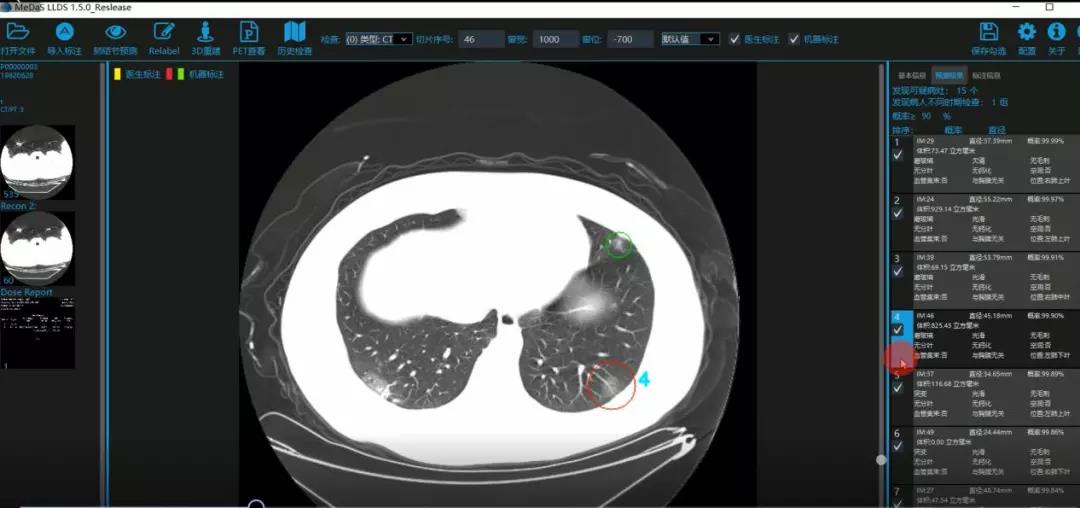

医护人员的好帮手:基于深度学习的新冠肺炎早期检测筛查系统

西电yl7703永利集团智能软件与系统新技术研究所副教授张亮的爱人是西安交通大学第二附属医院抗疫一线的影像科医生,疫情发生以来,他们讨论最多的就是新型冠状病毒感染者的早期诊断问题。作为一名医护家属,身为高校科研工作者,张亮深知快速准确地诊断新冠肺炎早期患者对控制和防治疫情的重要性和挑战性。他与团队成员主动出击,通过远程网络会议,在前期医学影像处理的研究基础上加速科研攻关,反复讨论方案,屡次设计模型,与上海宽带技术及应用工程研究中心、上海交通大学医学院附属瑞金医院等合作单位的人员多次标注整理患者肺部CT影像数据到深夜。与此同时,他们依托上海瑞金医院、西安交通大学第二附属医院等的新冠肺炎疑似、确诊患者肺部CT影像,通过综合分析新冠肺炎患者的肺部CT影像特点(磨玻璃、体积大小、位置等特征),张亮团队加快技术攻关,设计开发了基于深度学习的新型冠状病毒的早期检测筛查模型系统。

对应新冠肺炎CT病灶检测效果

令人欣喜的是,通过对实际门诊数据排查测试,该模型可以减轻医护人员近80%的工作量,新冠肺炎患者的检测召回率超过95%。目前,模型系统正在进行最后的调试工作,很快投入到“战疫”一线,缓解医护人员紧缺、确诊检测工作耗时较长等问题,减少医护人员的工作时间和劳动强度,提高工作效率。